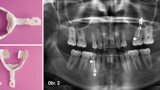

Implantace pomocí dynamické navigace s okamžitým zatížením